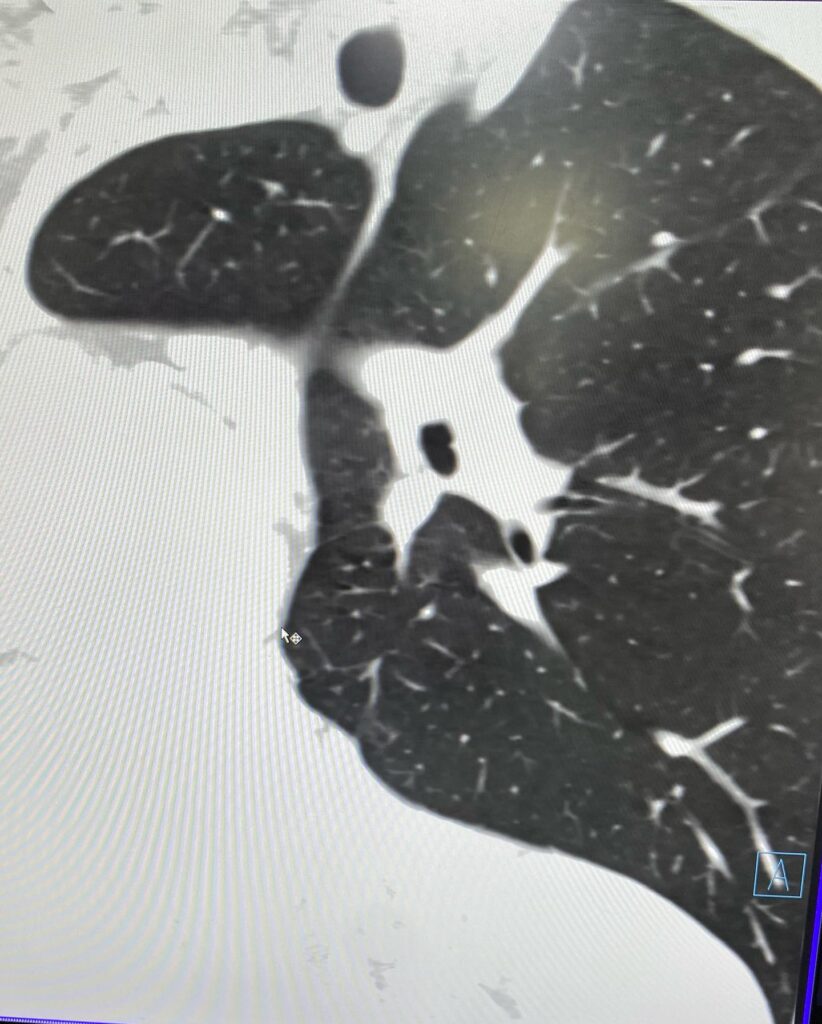

««Նորք-Մարաշ» բժշկական կենտրոն դիմելիս 14–ամյա տղայի գանգատը եղել է աջ կողմից սրտխփոցի զգացումը (մայրիկի խոսքերով՝ երեխան դա նկատել է դեռ 1 տարի առաջ ֆուտբոլ խաղալիս)։ Էխոսրտագրության ժամանակ երեխայի սիրտը աջից էր, սակայն դա սովորական դեկստրակարդիա չէր, ինչը բժշկի մոտ կասկած առաջացրեց, որի կապակցությամբ կատարվեց կրծքավանդակի կոնտրաստ համակարգչային տոմոգրաֆիա։

Արդյունքը տպավորիչ էր։ Երեխայի մոտ առկա էր աջ թոքի ագենեզիա (թոքը չի զարգացել, համապատասխանաբար բացակայում էին նաև աջ գլխավոր բրոնխը, աջ թոքային զարկերակը և աջ թոքային երակները), ինչի հետևանքով միջնորմը (այդ թվում սիրտը) տեղակայված է կրծքավանդակի աջ կեսում։ Սրտի նման տեղակայումը հեմոդինամիկ շեղումներ չի առաջացրել. երեխան ունի կառուցվածքային առողջ սիրտ։ Երեխան ուղեգրվել է թոքաբանի և օրթոպեդի խորհրդատվության, իսկ «Նորք-Մարաշ» ԲԿ-ում կլինի դինամիկ հսկողության տակ»,- հայտնում են «Նորք-Մարաշ» ԲԿ-ից։